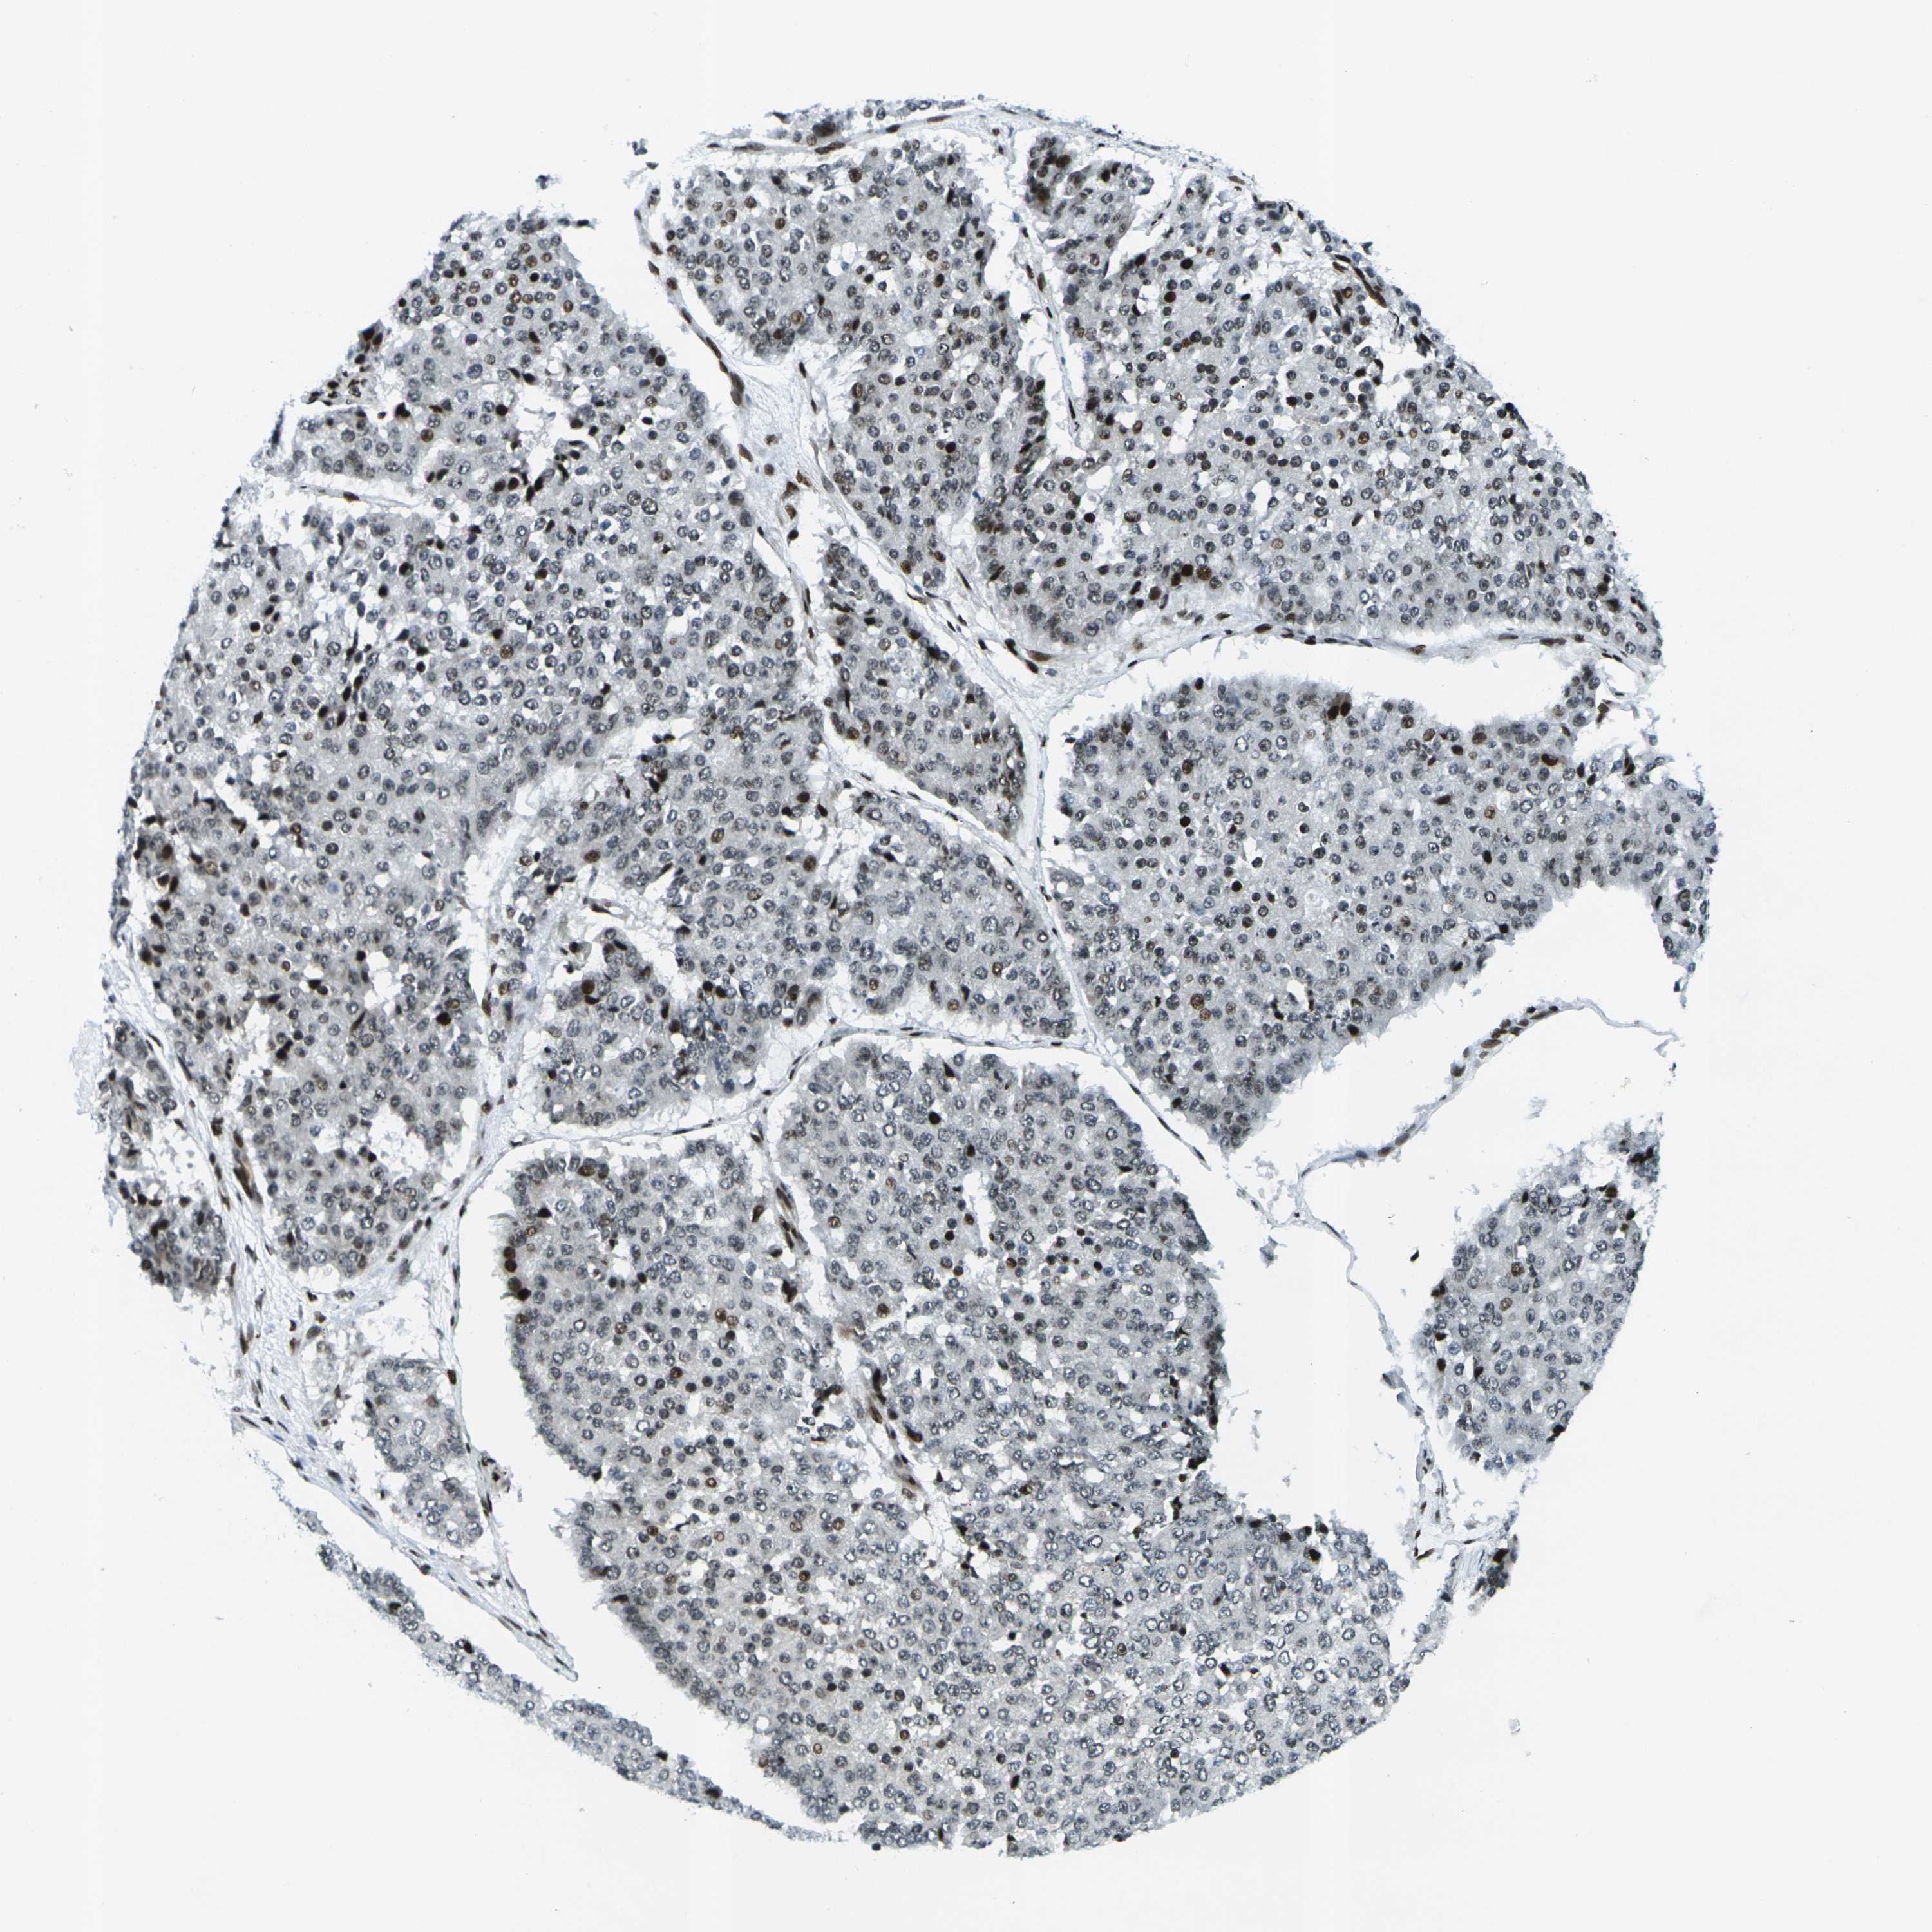

PANCREATIC CANCER - Protein expressioni

A mouse-over function shows sample information and annotation data. Click on an image to view it in a full screen mode. Samples can be filtered based on level of antibody staining by selecting one or several of the following categories: high, medium, low and not detected. The assay and annotation is described here.

Note that samples used for immunohistochemistry by the Human Protein Atlas do not correspond to samples in the TCGA dataset.

Antibody stainingi

Antibody staining in the annotated cell types in the current human tissue is reported as not detected, low, medium, or high, based on conventional immunohistochemistry profiling in selected tissues. This score is based on the combination of the staining intensity and fraction of stained cells.

Each image is clickable and will lead to virtual microscopy that enables deeper exploration of all samples and also displays staining intensity scores, fraction scores and subcellular localization as well as patient and tissue information for each sample.

Antibody HPA042570

Antibody CAB011481

Antibody CAB037178

Staining

High

Medium

Low

Not detected

Intensity

Strong

Moderate

Weak

Negative

Quantity

>75%

75%-25%

<25%

None

Location

Nuclear

Cytoplasmic/membranous

Cytoplasmic/membranous,nuclear

Adenocarcinoma, NOS

Adenocarcinoma, metastatic, NOS